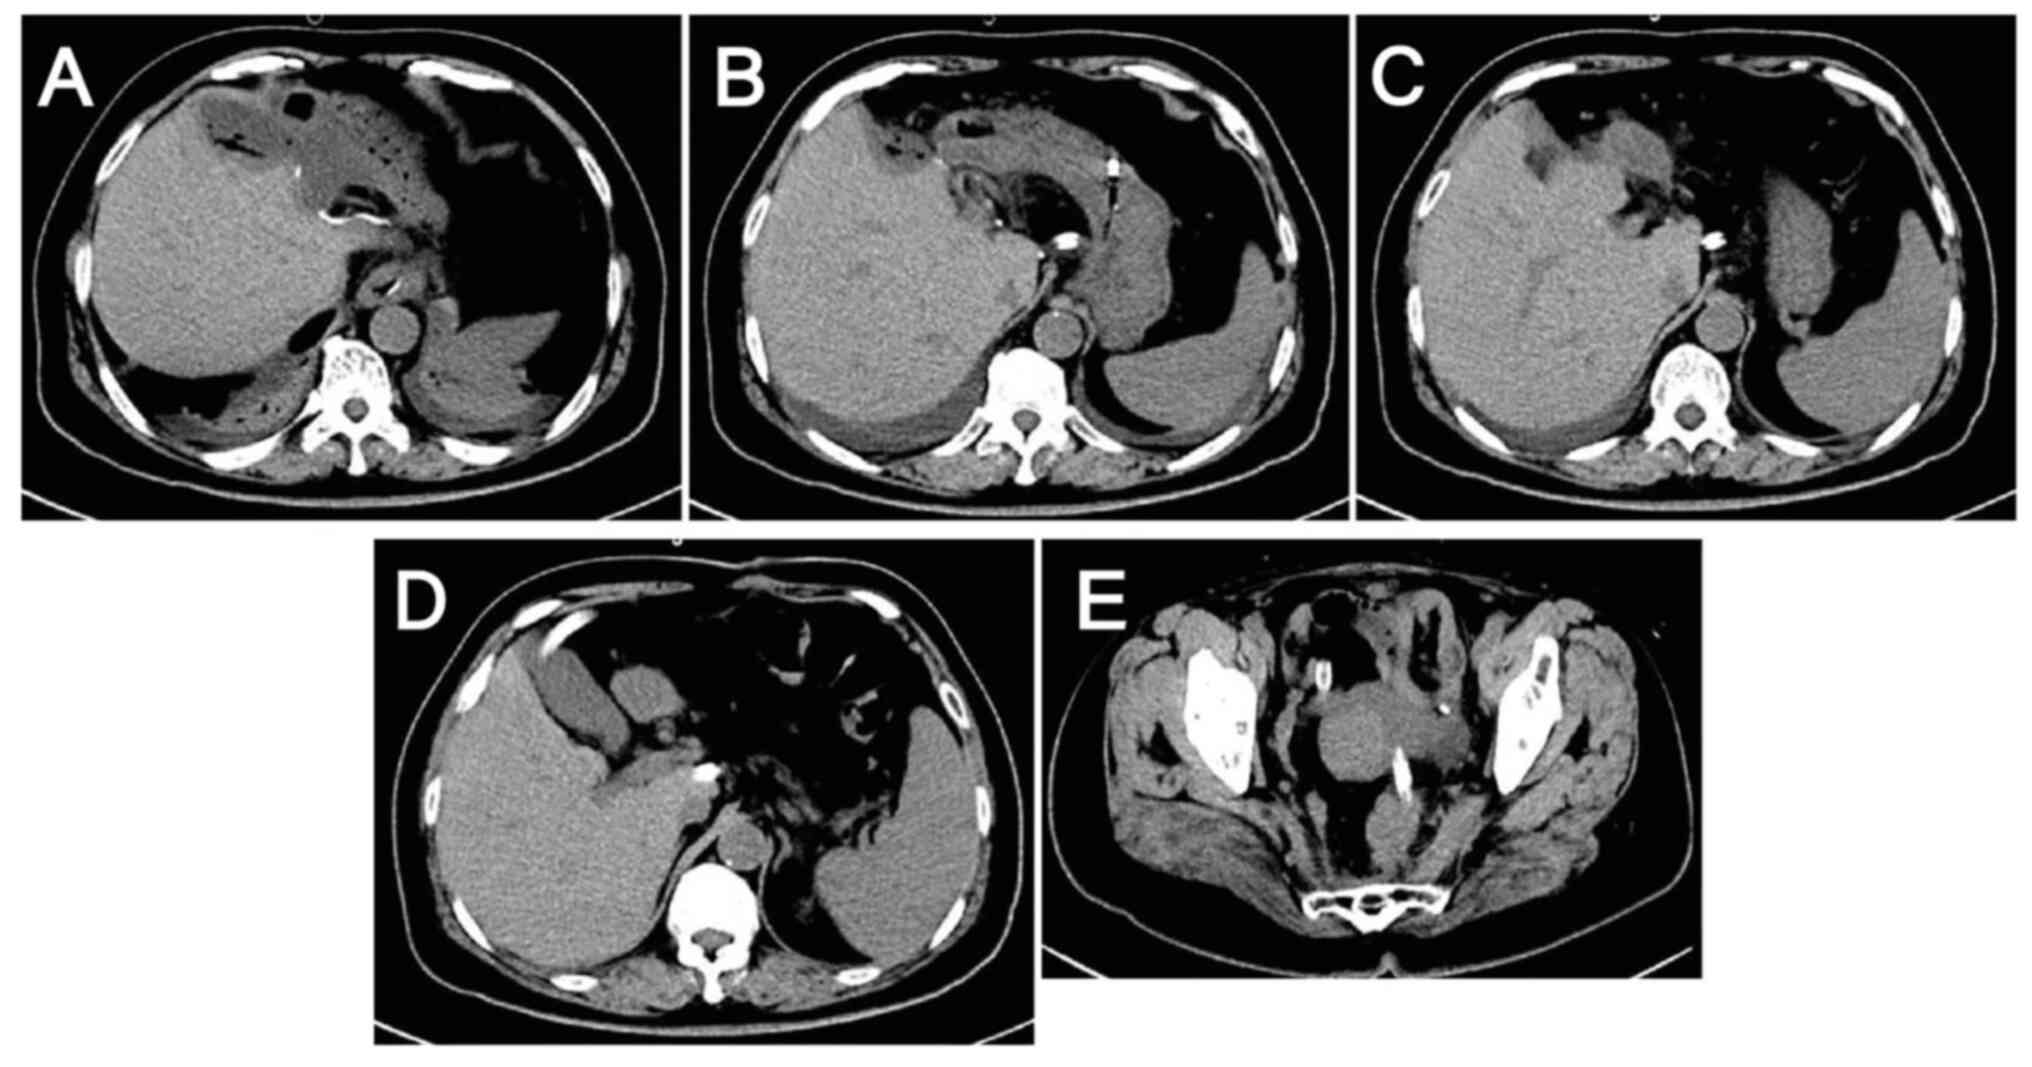

Lesions after 4 cycles of anti-HER2

therapy combined with chemotherapy as evaluated by computed

tomography on February 16, 2024. (A-D) Metastatic liver lesions:

Lesions are smaller compared with those on December 13, 2023. (E

and F) Colon lesions: Thickening of the sigmoid-rectal wall is

reduced and the surrounding lymph nodes are slightly smaller than

they were on December 13, 2023.

Figure 7.

Lesions after 4 cycles of anti-HER2 therapy combined with chemotherapy as evaluated by computed tomography on February 16, 2024. (A-D) Metastatic liver lesions: Lesions are smaller compared with those on December 13, 2023. (E and F) Colon lesions: Thickening of the sigmoid-rectal wall is reduced and the surrounding lymph nodes are slightly smaller than they were on December 13, 2023.

EGFR inhibitor therapy was not considered due to the NGS result and the evidence suggesting that patients with HER2-positive CRC are highly resistant to EGFR inhibitors (11,12). Furthermore, targeted bevacizumab therapy was not started because hemorrhage is one of the most serious adverse effects of bevacizumab and the patient had persistent hematochezia. In light of the recent developments in CRC research and the financial circumstances of the patient, single-agent anti-HER2 therapy combined with a modified FOLFOX6 regimen was selected as the subsequent treatment, in which the doses of chemotherapeutic agents were adjusted and administered on a 3-week cycle. The patient received six cycles of trastuzumab 450 mg + FOLFOX, with the latter comprising oxaliplatin 150 mg + leucovorin calcium 600 mg + fluorouracil 0.625 g by injection + fluorouracil 4 g by continuous intravenous drip. These agents were administered on 41 days post admission, 62 days post admission, 83 days post admission, 108 days post admission, 134 days post admission, and 157 days post admission. During treatment, the tumor marker levels gradually decreased (Fig. 4), and computed tomography (CT) and magnetic resonance scans of the liver indicated a marked reduction in the size of the tumor lesions (Fig. 6, Fig. 7, Fig. 8, Fig. 9). This was evaluated as a partial response.